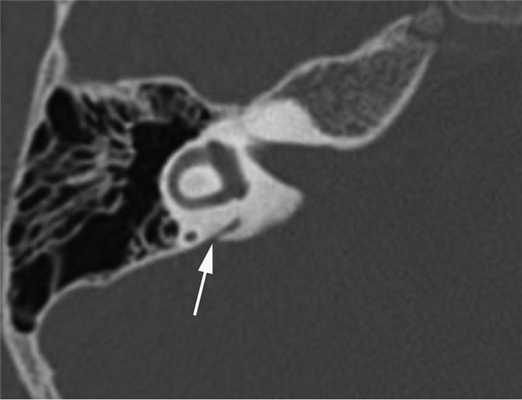

Прижизненная визуализация водопровода преддверия стала возможной с внедрением в клиническую практику компьютерной томографии (КТ). На томограммах неизмененный водопровод преддверия (рис. 1) визуализируется в виде узкой линейной щели шириной до 1,5 мм, идущей от преддверия к задней грани пирамиды и заканчивающийся на ней отверстием, расположенным кзади от внутреннего слухового прохода [3, 4].

Рис. 1. Неизмененный водопровод преддверия (стрелка). Компьютерная томограмма правой височной кости в аксиальной проекции.

Диагностика. СРВП часто мимикрирует заболевания среднего уха. Известно, что аномальное соединение внутреннего уха с подоболочечным пространством головного мозга, также как и «третье окно» лабиринта, может давать костно-воздушный разрыв на аудиограмме, более выраженный на низких частотах. Это явление описано в англоязычной литературе как интралабиринтная кондуктивная тугоухость, «псевдокондуктивная» тугоухость или «ложная» кондуктивная тугоухость [18]. Поэтому любое снижение слуха, характеризующееся нормальными тимпанограммами типа А, наличием акустических рефлексов и костно-воздушного интервала, более выраженного на низких частотах, должно вызывать подозрение на аномалию внутреннего уха. В таких случаях показано проведение высокоразрешающей мультиспиральной КТ височных костей, что позволит избежать эксплоративной тимпанотомии, проводимой ошибочно по поводу смешанной или кондуктивной тугоухости неясного генеза. На К.Т. данный синдром характеризуется расширением водопровода преддверия от 1,5 до 5—6 мм (рис. 2).

Рис. 2. Широкий водопровод преддверия (стрелка). Компьютерная томограмма правой височной кости в аксиальной проекции. Пациент А., 14 лет.